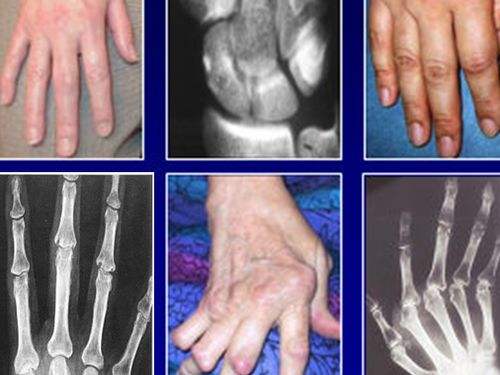

风湿和类风湿的区别你都知道吗

风湿和类风湿的区别你都知道吗,生活中很多老年人都有风湿病,也威胁着很多老年人的健康生活,很多人都把风湿和类风湿混合在一起了,那么你知道风湿和类风湿的区别吗?下面小编给大家讲解一下风湿和类风湿两者的区别。